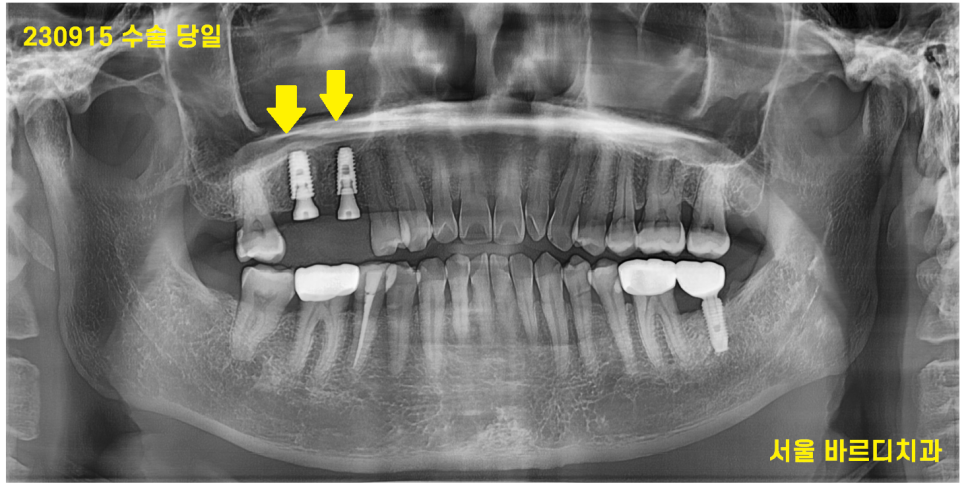

230915

드디어 심었습니다.

길고 긴 시간을 지나

6개월을 기다려

240102

9월달에 심고 이번에는 임플란트가

만들어놓은 뼈와 잘 붙어야합니다.

3개월을 추가적으로 기다렸습니다.